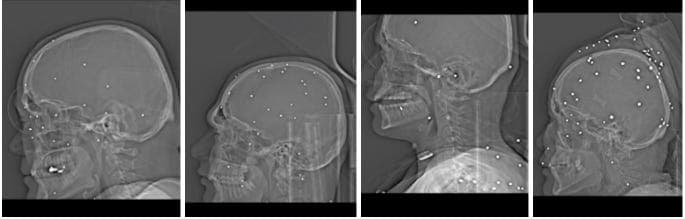

1. Head, face, eyes, and neck

A significant number of injuries involved the face and eye sockets, often with multiple shotgun pellets embedded around the orbit. Doctors repeatedly warned of a high risk of permanent blindness.

In some cases, pellets were lodged near the skull base or even inside the cranial cavity, raising the risk of brain injury, permanent neurological damage, or death.

One case showed a bullet in the neck causing tracheal displacement, with signs consistent with bleeding and swelling. Physicians noted the potential for major vascular injury, stroke, or fatal hemorrhage.